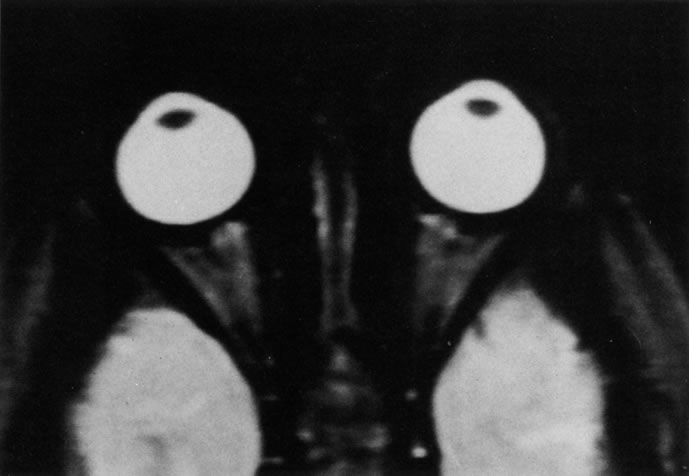

INTRAOCULAR TUMORS

On MRI, uveal melanomas have a typical appearance that helps to differentiate them from other primary and secondary intraocular tumors as well as choroidal detachments. Pigmented melanomas are hyperintense on Tl-weighted images, hypointense on T2-weighted studies, and hyperintense on proton density–weighted examinations (Fig. 24).30,31,50,80–82 These signal characteristics have been attributed to the paramagnetic properties of melanin because of stable free radicals that shorten the T1 and T2 relaxation times. Moderate enhancement is seen on postgadolinium T2-weighted images. Gadolinium-enhanced T1-weighted images are particularly sensitive in detecting choroidal melanomas.83 MRI may be less sensitive in detecting extrascleral extension of tumor than echography performed by an experienced ultrasonographer.84

Fig. 24. A. T1- and (B) T2-weighted MR scans demonstrate a small nodular intraocular mass (arrows) that is very hyperintense on the T1-weighted scan and hypointense on the T2-weighted image. This signal intensity pattern is due to the presence of free radicals within melanin granules. C and D. Postcontrast fat-suppressed T1-weighted scans demonstrate homogeneous intense enhancement of the lesion and no evidence of seleral penetration or optic nerve invasion.

Tumors metastatic to the choroid are hyperintense on T1- and T2-weighted images.24 The signal characteristics, however, may be similar to those seen with choroidal melanoma. Choroidal hemangiomas, on the other hand, have an intermediate signal on T1-weighted sequences and become hyperintense on T2-weighted images50 as well as proton density–weighted images.81

Retinoblastomas display moderate signal intensity on T1-weighted studies and a low signal on T2-weighted images.31,80,85 Calcification can be easily detected by CT and ocular ultrasonography but is not imaged by MRI.25,50 The presence of optic nerve involvement is best evaluated by MRI.